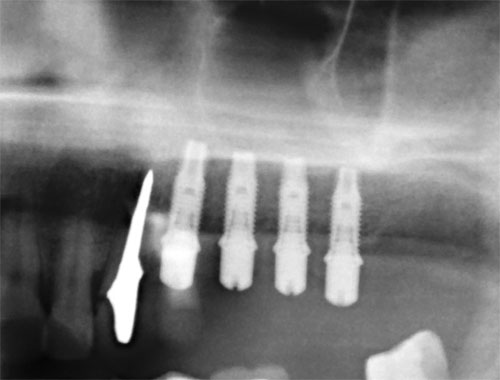

Имплантация →Синус-лифтинг

Синус-лифтинг (поднятие дна гаймеровой пазухи). Данная процедура относится только к верхней челюсти. Проводится в случаях недостаточной высоты кости между краем костного гребня верхней челюсти и дном гаймеровой (верхнечелюстной) пазухи. Различают открытый и закрытый синуслифтинг по способу доступа к пазухе. Закрытый — это доступ через отверстие импланта, а открытый — это боковой доступ через преддверие полости рта. Принцип операции в том, что через любой из доступов, в пазуху вводится костное вещество, которое превращается в собственную кость в течение полугода. В зависимости от толщины альвеолярного отростка зубные имплантаты могут быть установлены либо одновременно с выполнением синус-лифтинга, либо через некоторое время после заживления участка. статья «Синус-лифтинг» добавлена 2008-11-15 года